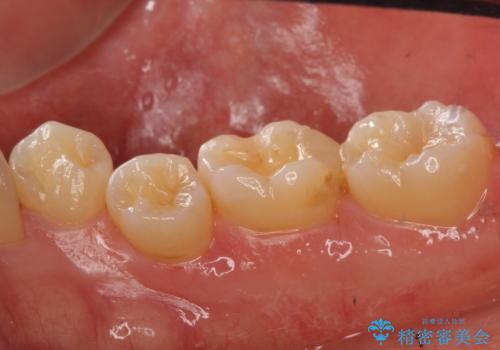

- 左下に詰めた樹脂の変色を主訴に来院されました。

同じ樹脂の材料で詰め直しをしたところでまた変色してしまうリスクが高いため、セラミックでの治療となりました。

樹脂の材料はどうしても変色などの劣化スピードが速いです。

樹脂の変色が気になる場合は、劣化しにくいセラミックに材料ごと変えることをお勧めします。